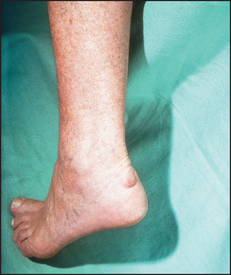

Note any swelling over the joint. There are a number of possible causes: these include effusion into the joint space, hypertrophy and inflammation of the synovium (e.g. rheumatoid arthritis), or bony overgrowths at the joint margins (e.g. osteoarthritis). It may also occur when tissues around the joints become involved, as with the tendinitis or bursitis of rheumatoid arthritis. Swelling of the lower legs may be due to fluid retention, which is painless and can occur in association with inflammation anywhere in the leg. Painful swelling may result from inflammation of the ankle joints or tendons, or of the fascia, or from inflammatory oedema of the skin and subcutaneous tissue.

There may be deformity involving the ankle or toes. Patients find this especially troublesome if it makes it difficult to put on shoes. The patient may have noticed swelling; ask if this is painful or not and whether it involves one or both feet. Bilateral swelling is more likely due to inflammation. Swelling over the medial aspect of the first metatarsal head (a bunion) occurs commonly as people get older, but may be associated with rheumatoid arthritis.